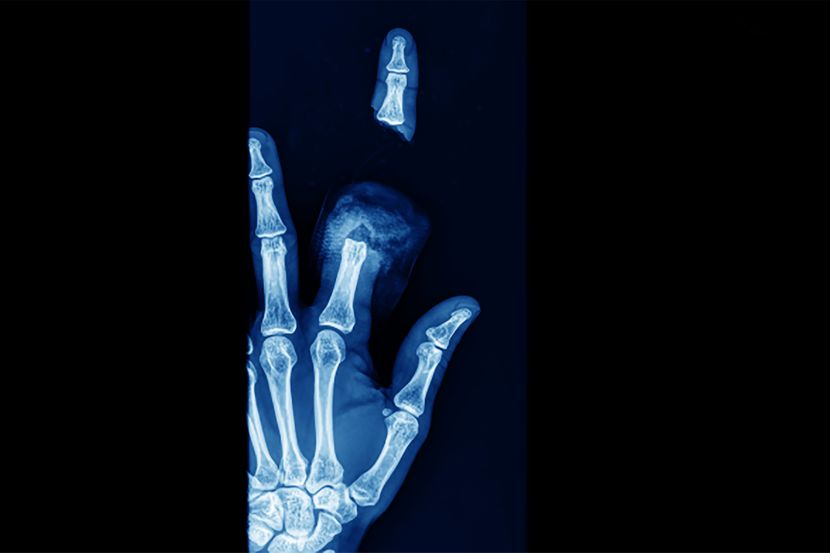

Ukazujući na svu složenost mikrohirurgije gornjih ekstremiteta, prof. dr Vučetić ističe, između ostalog, izuzetno složenu anatomsku i funkcionalnu građu šake, koja je vrlo čest predmet povreda. Šaka je deo sistema organa za kretanje i organ je od ključnog značaja za ukupno funkcionisanje čoveka, s obzirom na vrlo suptilan senzibilitet prstiju. Prezentacija senzibiliteta prstiju u kori velikog mozga je srazmerno mnogo veća u odnosu na druge delove tela, te je dodir prstima toliko specifičan u smislu pružanja brojnih informacija da se može uporediti sa čulom vida.